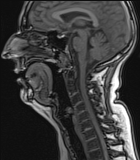

Forschung: 2D & 3D MRT Studie und Analyse von verschiedenen Gesangsstilen

Verschiedene Gesangsstile haben unterschiedliche Einstellung im Vokaltrakt.

Bei den MRT Studien geht es darum in 2D und 3D noch mehr Einblicke über den Vokaltrakt bei verschiedenen anatomischen Einstellungen zu bekommen.

Im Estill Voice Training trainiert man einzelne Strukturen des Vokaltrakts. Dadurch ist es möglich sehr spezifisch Klangfarben zu produzieren. Die verschiedenen Qualitäten dieser Technik werden untersucht: Speech, Falsetto, Sobbing, Twang, Opera, Belting